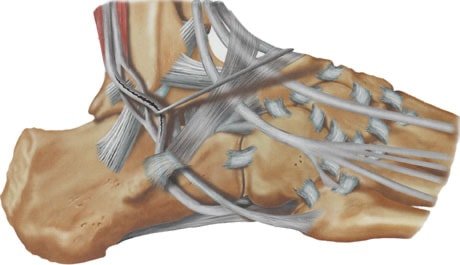

I tendini sono bendellette di tessuto elastico che connettono un muscolo all’osso al quale devono trasmettere la loro azione meccanica. I due tendini peronieri decorrono all’esterno delle ossa nella caviglia, uno di essi prende inserzione sulla parte esterna del mesopiede l’altro invece curva sotto al piede inserendosi all’interno della volta plantare stabilizzandola trasversalmente.

la principale funzione dei tendini peronieri è quella di stabilizzare il piede e la caviglia proteggendo i legamenti da stiramenti e rotture.

Le lesioni dei tendini peronieri possono essere acute o croniche. Frequentemente occorrono ad individui che praticano sport di contatto, comportanti ripetuti movimenti della caviglia. I soggetti con piede cavo sono più predisposti a questo tipo di affezioni, a causa della rotazione in varo del calcagno che sottopone a maggior tensione i due tendini.

Sarà compito del chirurgo esperto, quello di escludere lesioni molto spesso associate, come quelle della capsula e dei legamenti laterali della caviglia, dei legamenti dell’articolazione sottoastragalica e delle sindesmosi che tengono uniti il perone alla tibia.